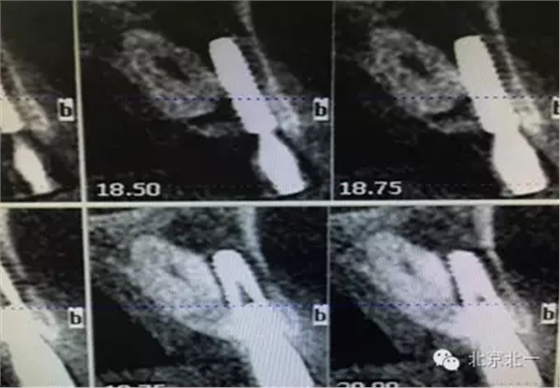

患者種植一月后種植區(qū)不適,偶有疼痛來(lái)院拍片發(fā)現(xiàn)23埋伏牙,與種植體相鄰,如圖一、二、三、四所示。